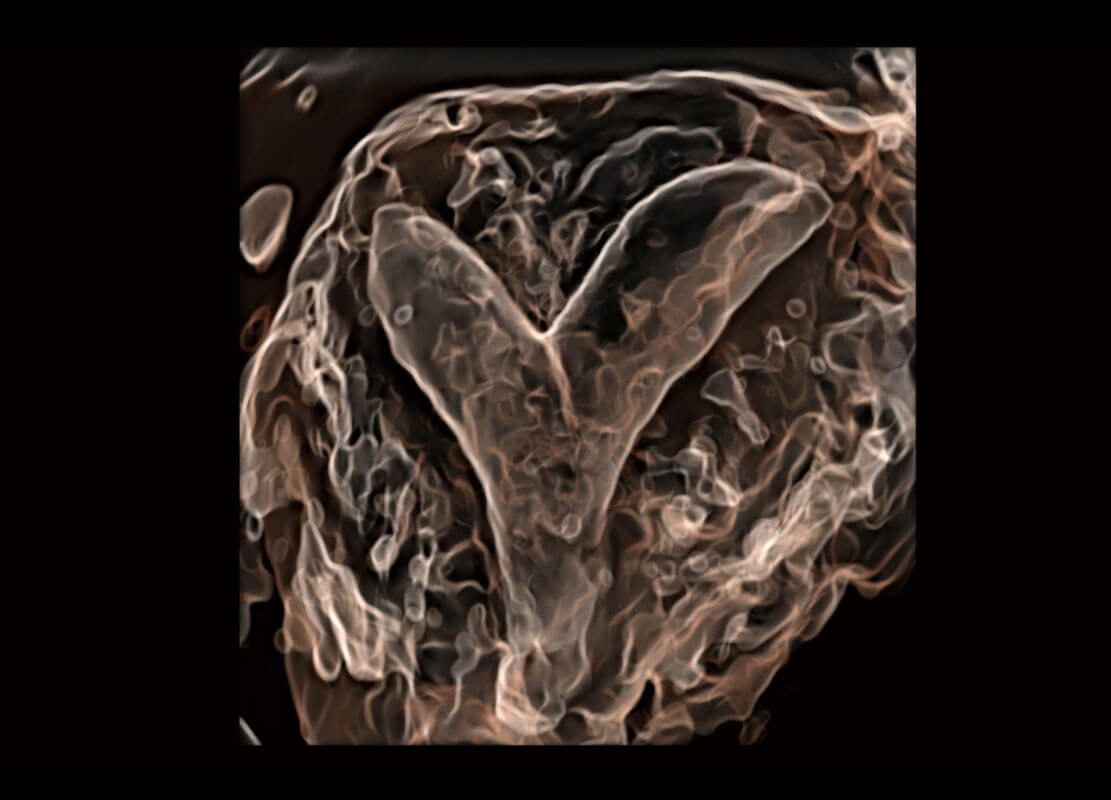

• 腔内三维-光影成像

• 光影成像-孕囊